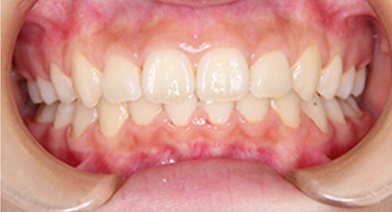

- 治療前 治療後

| 症例タイトル | 過蓋咬合 |

| 治療内容 | かみ合わせが深く、下顎が後方におしこめられているケースになります。 まず、バイトプレートによるかみ合わせの高さ、下顎の前方適応のコントロールをした後、ワイヤーを装着しました。 下顎の前方適応が難しいケースは、上顎の大臼歯の遠心移動が必要なこともあります。 |

| 患者さまの年齢 | 10代 |

| 患者さまの性別 | 女性 |

| 治療期間 | 1年4ヶ月 |